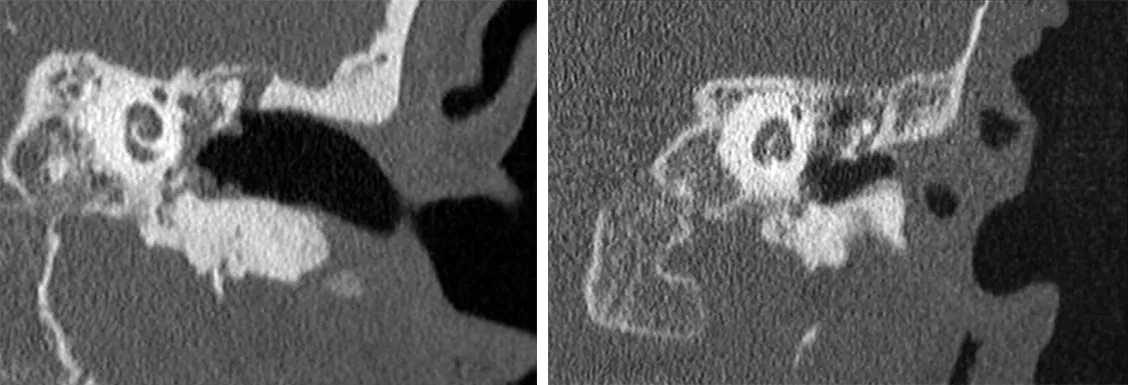

• TC de oído medio: la tomografía computarizada de alta definición es la prueba de imagen de elección en el diagnóstico del colesteatoma por su gran resolución espacial.

Los hallazgos típicos en el TC son: la presencia de retracción de la membrana timpánica, una lesión de partes blandas expansiva que erosiona el hueso haciendo desaparecer parcial o completamente el scutum, que es el borde óseo lateral del receso epitimpánico, pudiendo afectar también a la cadena de huesecillos y al tegmen tímpani que es la estructura ósea de la base del cráneo que separa el oído medio de la fosa media craneal que aloja el lóbulo temporal del cerebro.

Sup. Imagen sugerente de colesteatoma. Masa que ocupa la caja timpánica con erosión del scutum y del tegmen tímpani.

Inf. Ocupación de caja timpánica derecha, sin erosión ósea, que sugiere una otitis media no colesteatomatosa.

Cuando encontramos la ocupación de todo el oído medio por partes blandas pero no se observan signos de erosión ósea, debemos sospechar de la presencia de una otitis media crónica sin colesteatoma.

Es decir, el signo radiológico diferenciador del colesteatoma es la erosión ósea, con la excepción del colesteatoma primario en el que la dicha erosión es poco frecuente, por lo que la ausencia de esta tampoco excluye definitivamente el colesteatoma, sobre todo en lesiones pequeñas y poco evolucionadas. Por otro lado, el contraste de la TC tampoco es muy específico.

El valor predictivo negativo es muy alto por lo que es muy fiable el diagnóstico de exclusión. Sin embargo, el diagnóstico positivo no está exento de errores.